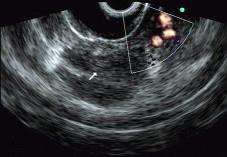

问题 男性,50岁,上腹隐痛,食欲不振3个月。1个月来出现黄疸且进行性加深,体重明显减轻,查体全身明显黄染,肝未触及,深吸气时可触到肿大胆囊底部,无触痛。化验血胆红素15mg/dl,尿检胆红素阳性图中胰腺病变可能的诊断是 ( )

选项 A、胰腺囊腺癌 B、胰腺癌 C、胰腺囊肿 D、慢性胰腺炎 E、正常

答案 B